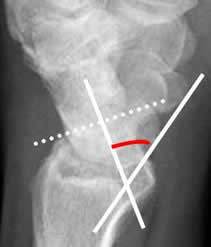

MUÑECA:

Inclinación radial:

Se traza con una línea perpendicular al eje del radio y otra línea a lo largo de su superficie distal. El valor normal es entre 16º y 28º. (12). Este ángulo disminuye en fracturas metafisisarias, impactadas, de Colles y Smith. Debe ser valorado después de la reducción e inmovilización, para dejarlo lo mas normal posible y que permita una adecuada movilidad. (1). (Fig 46).

Fig 46. Inclinación radial.

Rx AP. Angulo formado entre la perpendicular al eje del radio y una línea que pasa por la superficie articular distal, del mismo hueso.